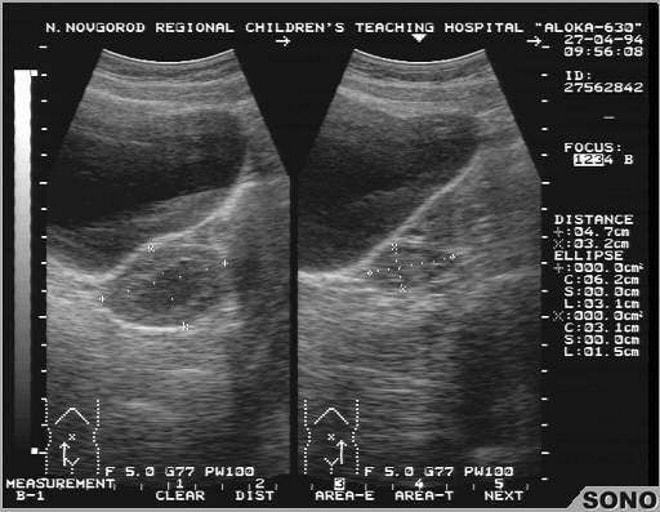

- УЗИ органов малого таза – дает точные данные о размерах половых органов и наличии воспалительных процессов;